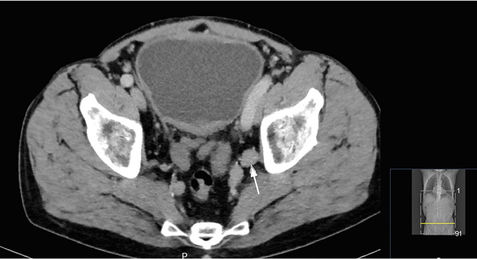

Ein 62-jähriger Patient stellt sich bei seinem Hausarzt mit einer seit zwei Tagen bestehenden Makrohämaturie vor. Zur weiteren Abklärung wird beim niedergelassenen Urologen eine Zystoskopie durchgeführt. Hier zeigt sich ein etwa 4 cm großer breitbasiger Tumor. Daraufhin stellt sich der Patient in unserer Klinik zur transurethralen Resektion des Harnblasentumors (TUR-Blase) vor. Histologisch wird ein muskelinvasives Urothelkarzinom der Harnblase nachgewiesen. Zum weiteren Staging wird ein Kontrastmittel-CT von Thorax, Abdomen und Becken durchgeführt. Hier zeigen sich keine Fernmetastasen oder Pathologien des oberen Harntraktes. Allerdings findet sich der Verdacht auf drei pelvine Lymphknotenmetastasen von bis zu 3 cm Größe (Abbildung 4).

Abbildung 4: Staging-CT mit pelvinen Lymphknotenmetastasen

Bei dem Patienten liegt folglich ein muskelinvasives Urothelkarzinom der Harnblase mit dem Verdacht auf eine lokoregionäre Lymphknotenmetastasierung vor (pT2, cN2, cM0). Als multimodales Konzept haben wir dem Patienten eine induktive, cisplatinbasierte Kombinationschemotherapie und anschließend die Durchführung einer Zystektomie mit Anlage einer Ileum-Neoblase empfohlen. Wegen der Nephro-, Oto- und Neurotoxizität von Cisplatin gibt es definierte Kriterien, die eine Gabe von Cisplatin verbieten (ECOG ≥ 2, Kreatinin-Clearance < 60 ml/min, Hörverlust ≥ Grad 2, Neuropathie ≥ Grad 2, Herzinsuffizienz NYHA ≥ III) [27]. Bei weiterreichender Niereninsuffizienz bis zu einer GFR von 40 ml/min kann die Gabe von Cisplatin auf zwei Tage verteilt werden (Split-dose-Schema) [28], unter einer GFR von 40 ml/min ist eine Gabe von Cisplatin in der Regel nicht möglich.